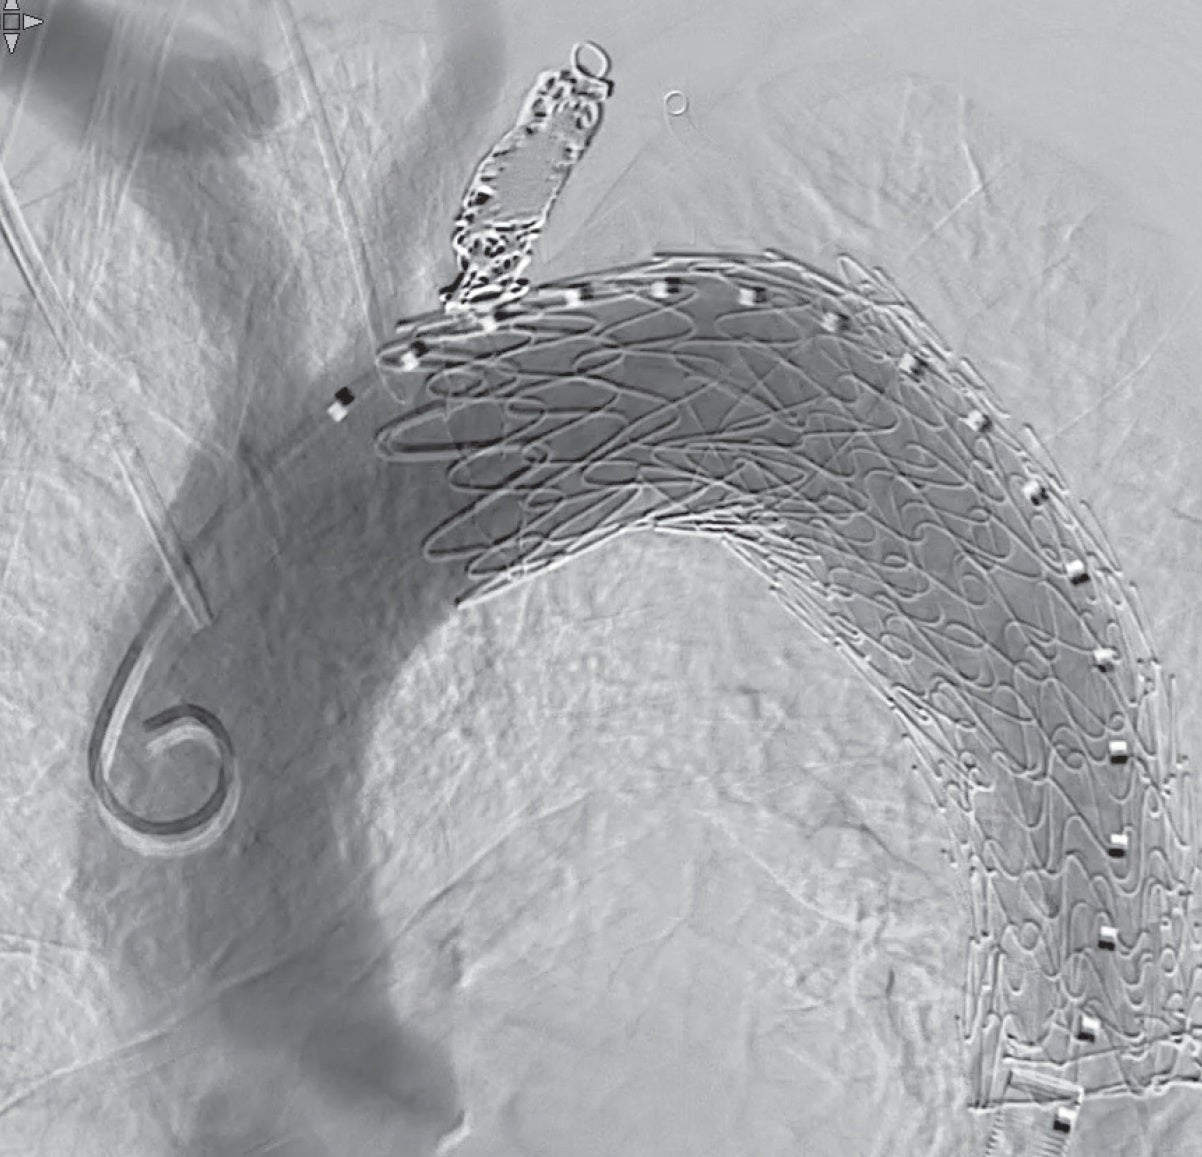

ドライシール フレックス イントロデューサシース内に1本目のTAG® コンフォーマブル ステントグラフト(TGM343410J)を挿入し、ドライシール フレックス イントロデューサシースをEVAR時のように抜退して(図 3b)、大動脈頂部(Zone 3近く)から末梢のランディングゾーンまでステントグラフトでカバーするように静かに展開する。シースとステントグラフトで「 鋪装 」された経路を通して中枢用の2本目のTAG® コンフォーマブル ステントグラフト(TGMR404015J)をZone 2まで先進させ、左鎖骨下動脈バルーンプロテクション下にゆっくり展開して、予定したデバイスを留置した(図5a, b)。

手術室で抜管し、脳梗塞、対麻痺、および腹部下肢の血栓塞栓症は認めなかった。術後1年半で重症大動脈弁狭窄症に対する経カテーテル大動脈弁留置術および下行大動脈嚢状動脈瘤への追加TEVARを施行した。2024年7月執筆時点で3年が経過するが、CT上エンドリークおよび瘤径拡大なく外来通院している。